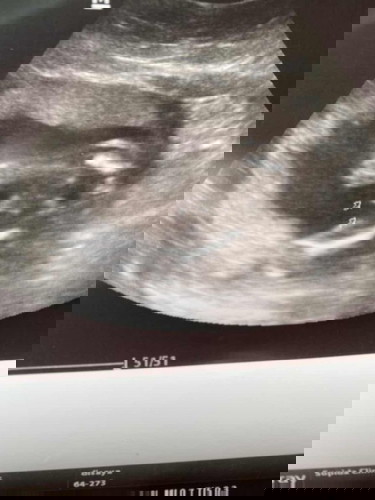

บ้านนี้ไปมาเมื่อวานหมอบอกว่าได้ผู้หญิงเพราะไม่มีอะไรโผล่มา ของแม่น่าจะได้ผู้ชายค่ะ😊😊

คุณหมอพิมพ์ไว้ว่า M=Male คิดว่าน่าจะเป็นผช.นะคะ 🥰🥰 ยินดีด้วยจ้า

เห็นเหมือนจุ๊ดจู๋น้อง น่าจะชายค่ะแม่ 😄

ชัดขนาดนี้น่าจะผู้ชายจ้า

จู๋แน่นอนค่ะแม่ 😂

ชายแน่ๆ เลยค่ะ 🥰